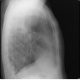

Здравствуйте, уважаемые колеги! Согласен с Андреем Юрьвичем. Состояние после правосторонней верхнедолевой лобэктомии. Средняя доля справа ушла вверх (природа не любит пустоты). Викарная эмфизема левого легкого. Спайки, фиброз, правосторонний фиброторакс. Но справа в проекции S6 полость с горизонтальным уровнем жидкости - хорошо видно на боковом. Может в междолевой щели осумкованный плеврит, абсцесс, эмпиема. Хотелось бы знать немного больше анамнеза, кроме операции. Боли, кашель, температура, изменения в анализе крови и т.д.

В проекции С6 уровень вижу, апикально нет. За абсцесс не вижу четкой нижней границы. Осумкованные междолевые не дают уровень. Ограниченную послеоперационную эмпиему не исключаю на фоне рассасывающегося геморрагического плеврита и фиброторакса...

- Не удивительно, при таком то качестве бокового снимка. Возьмите на скопию и убедитесь (кстати он не один)